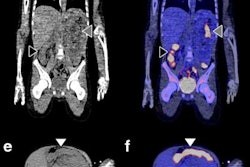

For this retrospective analysis, the researchers collected data from 36 patients who underwent a total of 128 PET scans of the kidneys, liver, lung, and spleen at Amsterdam University Medical Center; Centre Hospitalier Régional at the Universitaire de Lille in Lille, France; and Memorial Sloan Kettering Cancer Center in New York City. The exams were conducted over one to seven days after injection with an appropriate Zr-89-labeled antibody to image their tumors. The four Zr-89-labeled antibodies were Zr-89 obinutuzumab, Zr-89 cetuximab, Zr-89 huJ591, and Zr-89 trastuzumab. Nonspecific uptake was defined as activity measured in tissues without known target expression, which is to say, normal tissue.

Jauw and colleagues were able to quantify nonspecific uptake of monoclonal antibodies in normal tissue using Zr-89 immuno-PET at multiple time points during the seven-day period. By having this data from antibody distribution to normal tissues and tumors, the researchers believe they can enhance their knowledge of which drugs will be effective and, conversely, which drugs are likely to cause toxicity in cancer patients.

"Usually, Zr-89 immuno-PET scans are analyzed at a single time point, representing the sum of all physiologic components of antibody distribution, being either target-specific or nonspecific," the researchers explained. "This study showed how the various physiologic components of antibody distribution contribute to the measured SUV."